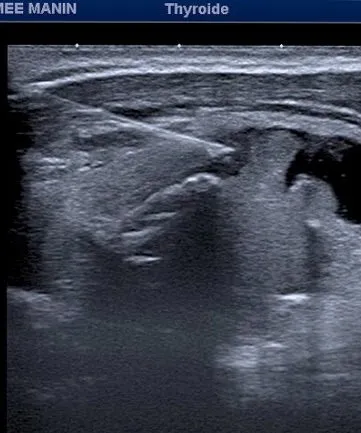

Sous Guidage Échographique : Prélèvement de cellules d'un nodule thyroïdien à l'aide d'une aiguille fine pour une analyse cytologique, déterminant la nature bénigne ou maligne du nodule.